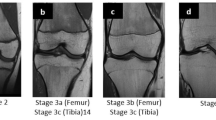

The examinations of the volunteers were sorted separately for both sexes from youngest to oldest. In a first step, all slices of each examination were then looked through to get an overview of the general morphology of the growth plate and the process of its ossification. This was done without knowledge of the exact age of the volunteers. In a second step, sketches of the found characteristics and changes of the growth plate were drawn for both sequences. Here, the separation by sex was dropped since unlike the chronology of the ossification the morphology of the growth plate showed no sex-related differences. Only characteristics that could be found alike in most cases of similar age were taken into account. At this point a distinct continuum of the growth plate’s development could be recognised. The sketches were then sifted for easily identifiable changes, i.e. the presence or absence of certain features. These morphological features were then put into an ascending order and the following staging system was formulated as a hypothesis (see Figs. 1 and 2 for the corresponding schematics and examples; see Table 2 for the shortened version):

Schematic drawings for the stages of the T2 TSE SPIR sequence and examples (3.0 T; non-contrast enhanced; coronal slice orientation); from left to right: male 13 years, male 14 years, female 16 years, male 20 years, female 22 years. MRI magnetic resonance imaging; TSE turbo spin echo; SPIR signal pre-saturation with inversion recovery

Stage 2: In the T1-w sequence a continuous band of intermediate signal intensity is visible, walled by serrated lines of low to no signal intensity towards the epiphysis and the diaphysis.

In the T2-w sequence the epiphysis is demarcated by a serrated line of low to no signal intensity. The metaphysis shows two serrated lines of high signal intensity. Both lines can be continuous or discontinuous.

Stage 3: In the T1-w sequence a discontinuous band of intermediate signal intensity is visible. The band is walled by serrated lines of low to no signal intensity towards the epiphysis and the diaphysis that sporadically convene and interrupt the band, forming a single serrated line with no signal intensity.

In the T2-w sequence the metaphysis shows two serrated lines of high signal intensity that sporadically convene, forming a single thin and serrated line of high signal intensity.

Stage 4: In the T1-w sequence a discontinuous thin and serrated line of intermediate signal intensity between the epiphysis and the diaphysis is visible. In the continuity of the line, thicker sections with no signal intensity can be seen.

In the T2-w sequence a thin single, discontinuous or dotted line of hyperintense signal is visible in the same position as the described thin line of the corresponding T1-w sequence. In the continuity of the line, thicker hyperintense sections can be seen.

Stage 5: In the T1-w sequence a continuous thin line of intermediate signal intensity between the epiphysis and the diaphysis is visible.

The T2-w sequence shows a single thin, discontinuous or dotted line of hyperintense signal in the same position as the described thin line of the corresponding T1-w sequence.

Stage 6: In the T1-w sequence a continuous thin line of intermediate signal intensity between the epiphysis and the diaphysis is visible.

The T2-w sequence shows no hyperintense signal in the same position as the described thin line of the corresponding T1-w sequence.

The stages are based on the presence or absence of certain landmarks of the epiphyseal-diaphyseal fusion’s morphological appearance, mainly drawn from the T1-w sequence. In the T1-w sequence they are characterised by the presence of a continuous band-like morphology of the growth plate (stage 2), the presence of a discontinuous band-like morphology (stage 3), the beginning thin-lined demarcation of the fusion’s “scar” (stage 4), the completely demarcated fusion’s “scar” with a corresponding T2-hyperintense signal (stage 5) and finally without a corresponding T2-hyperintense signal (stage 6). Stages 5 and 6 have the exact same appearance in the T1-w sequence and cannot be further differentiated without the T2-w sequence.